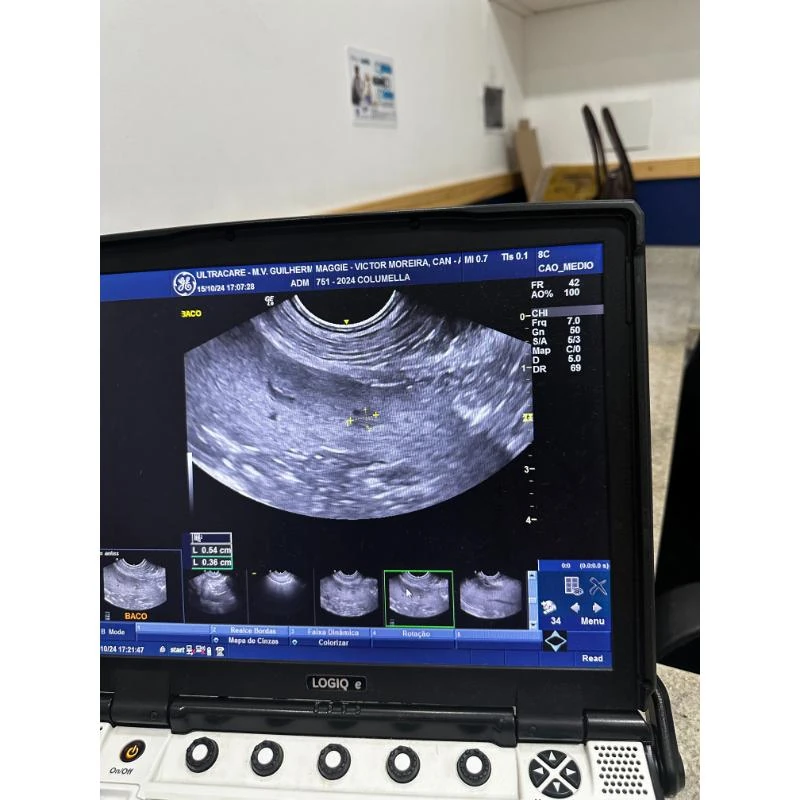

Na Columella Centro Veterinário, a consulta é realizada de forma completa e personalizada, com avaliação clínica detalhada, exames diagnósticos e orientações específicas para cada pet.

O objetivo é identificar precocemente alterações de saúde e planejar tratamentos adequados, promovendo o bem-estar e a prevenção de doenças.

A emergência para gatos é conduzida com atenção e técnica especializada na clínica, oferecendo suporte contínuo, exames rápidos e cuidados específicos para cada animal.